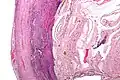

Pathology diagnosis of appendicitis can be made by detecting a neutrophilic infiltrate of the muscularis propria.

Micrograph of appendicitis and periappendicitis. H&E stain

Micrograph of appendicitis showing neutrophils in the muscularis propria. H&E stain